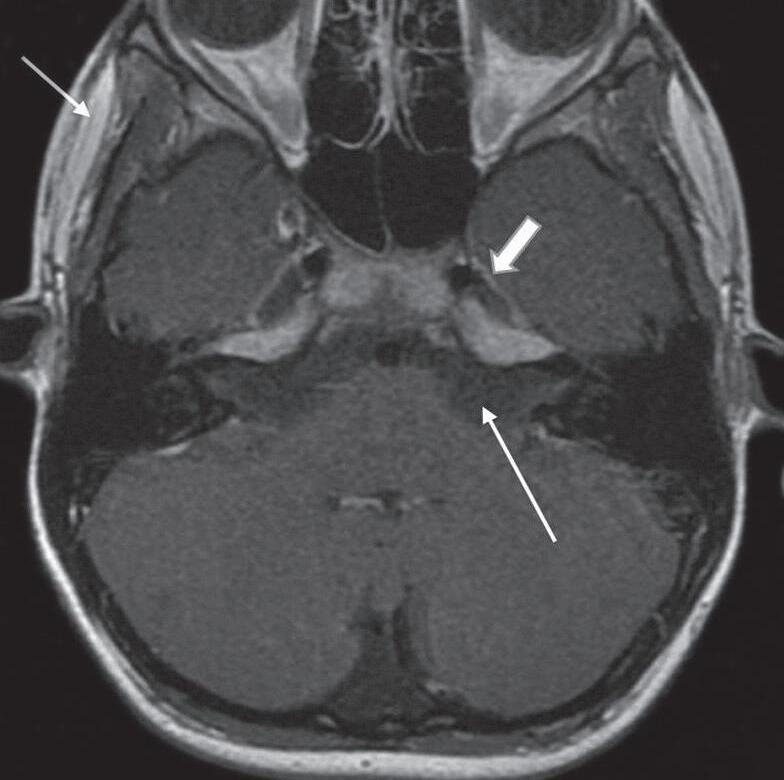

Sequências ponderadas em T1 sem e com supressão de gordura demonstram lesões com componentes de gordura. A gordura apresenta sinal hiperintenso nas sequências spin-eco rápidas T1 e T2, evanesce nas imagens adquiridas com supressão de gordura (Fig. 1-14).

A sequência com supressão de gordura deve ser utilizada na investigação de lipomas, já que a gordura evanesce nesta sequência; para excluir sangue, conteúdo proteico elevado, metemoglobina ou melanina que apresentam sinal hiperintenso em T1 e não evanescem na sequência com supressão de gordura; na avaliação de lesões adjacentes à medula óssea da base do crânio, face ou orelhas que apresentam sinal hiperintenso na sequência T1, possibilitando melhor demonstração da impregnação pelo agente paramagnético, apagando a gordura da medula óssea e destacando o realce pelo meio de contraste (Figs. 1-15 e 1-16).

1-15. Granuloma de colesterol no ápice petroso: TC dos ossos temporais: lesão expansiva no ápice petroso com atrofia óssea de pressão de suas paredes (seta longa); canal carotídeo (seta curta).

Fig. 1-16. Granuloma de colesterol no ápice petroso: RNM sequência axial T1 (a): lesão expansiva no ápice petroso, comprimindo a ponte, compatível com granuloma de colesterol, com sinal hiperintenso na sequência T1 (seta curta); liquor com sinal hipointenso (seta branca larga); gordura subcutânea com sinal hiperintenso na sequência T1 (seta preta longa). RNM sequência axial T1 com supressão de gordura; (b): a lesão persiste com sinal hiperintenso na sequência T1 com supressão de gordura (seta); liquor no quarto ventrículo com sinal hipointenso (seta larga); gordura subcutânea suprimida. RNM axial T1 com subtração das sequências pré e pós-gadolínio; (c): demonstra apenas áreas de impregnação pelo agente paramagnético, na periferia do granuloma de colesterol (seta). RNM axial T2; (d): lesão expansiva no ápice petroso com depósito periférico de hemossiderina, halo de sinal hipointenso (seta curta); liquor com sinal hiperintenso no quarto ventrículo (seta longa).